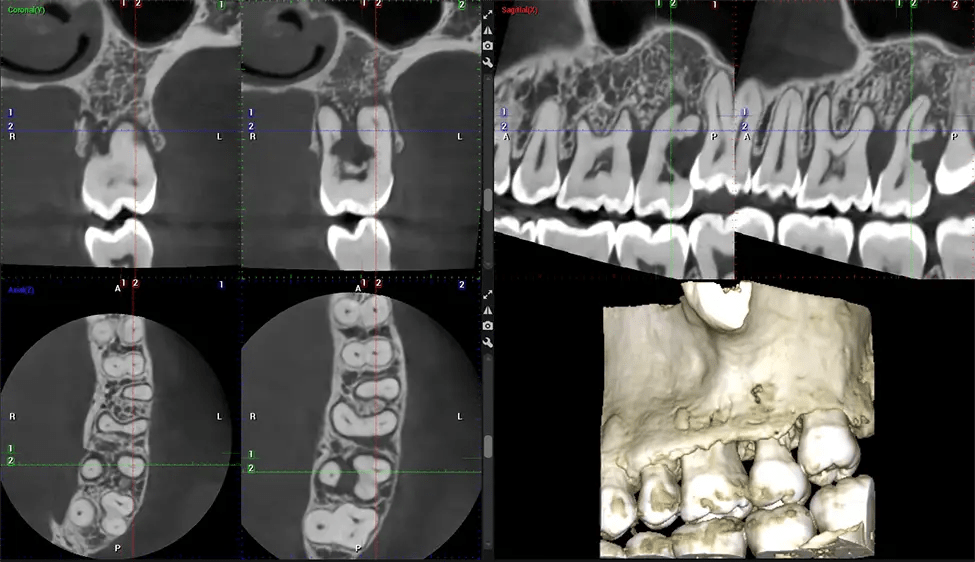

This 3D scan, called cone beam computed tomography, gives your dentist a more complete image of your oral anatomy and disease processes than a traditional X-ray. Unlike conventional X-rays, which capture a 2D image of your mouth from various angles, a 3D scan takes multiple digital X-rays for one image. It provides a complete view of your jaw, teeth, nerves, and soft tissues. This enhanced view allows dentists to detect minor issues not visible in traditional 2D scans, such as impacted wisdom teeth or bone fractures in the sinus cavity.

Another significant benefit is that 3D imaging provides more precise images of your bone structure. These images are more detailed, providing you with a more accurate diagnosis. An accurate diagnosis means better treatment for you.

After the scanning process, the captured X-ray images are processed by the CBCT software, which applies algorithms to reconstruct a detailed 3D image of the scanned area. The software compiles these individual X-ray images and creates a digital 3D representation of the patient’s anatomy. The reconstructed 3D CBCT image can be viewed and analyzed by the dentist or radiologist. This image can be manipulated, rotated, and zoomed in or out to examine specific structures and evaluate the patient’s condition.

Our patented SCARA technology enables doctors to capture True Extraoral Bitewings that are as accurate at detecting caries as a 2D bitewing series, but with half the radiation dose. With our bitewings, doctors can view the apices of teeth on both jaws providing a more comprehensive view of the patients’ anatomy.

Planmeca 3D systems come with Autofocus, a technology that produces incredibly clear panoramic images, even on the interiors. This technology sets our 2D images apart from the competition.